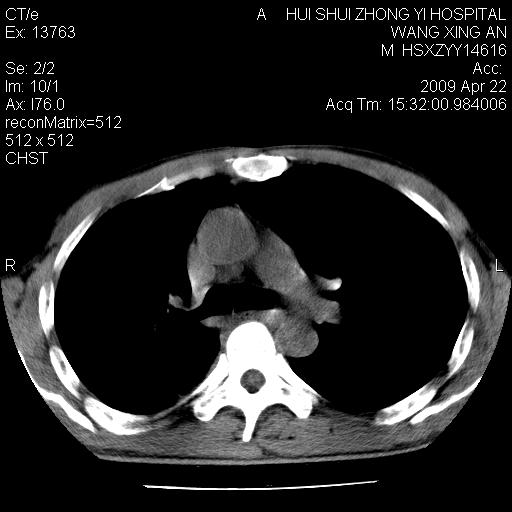

标题: CT19534:患者男、46岁咳嗽、胸痛半月。 [打印本页]

标题: CT19534:患者男、46岁咳嗽、胸痛半月。

考虑---右肺中心型肺癌继发下叶不张,少量胸水。

支持右侧中央型肺ca并右下肺不张、右侧胸腔少量积液。

1、右下肺中央型肺癌并右肺转移,右肺下叶不张。(右肺有结节影)。

2、右中上肺陈旧性肺结核(因为大多为纤维灶)。

3、右侧胸腔积液。

1、右下肺中央型肺癌并右肺转移,右肺下叶不张。(肿块围绕右肺下叶支气管生长,致管腔闭塞右肺下叶不张;右肺有结节影)。

2、右侧胸腔积液。

3、右中上肺陈旧性肺结核(右肺见纤维化病灶及点状钙化)。